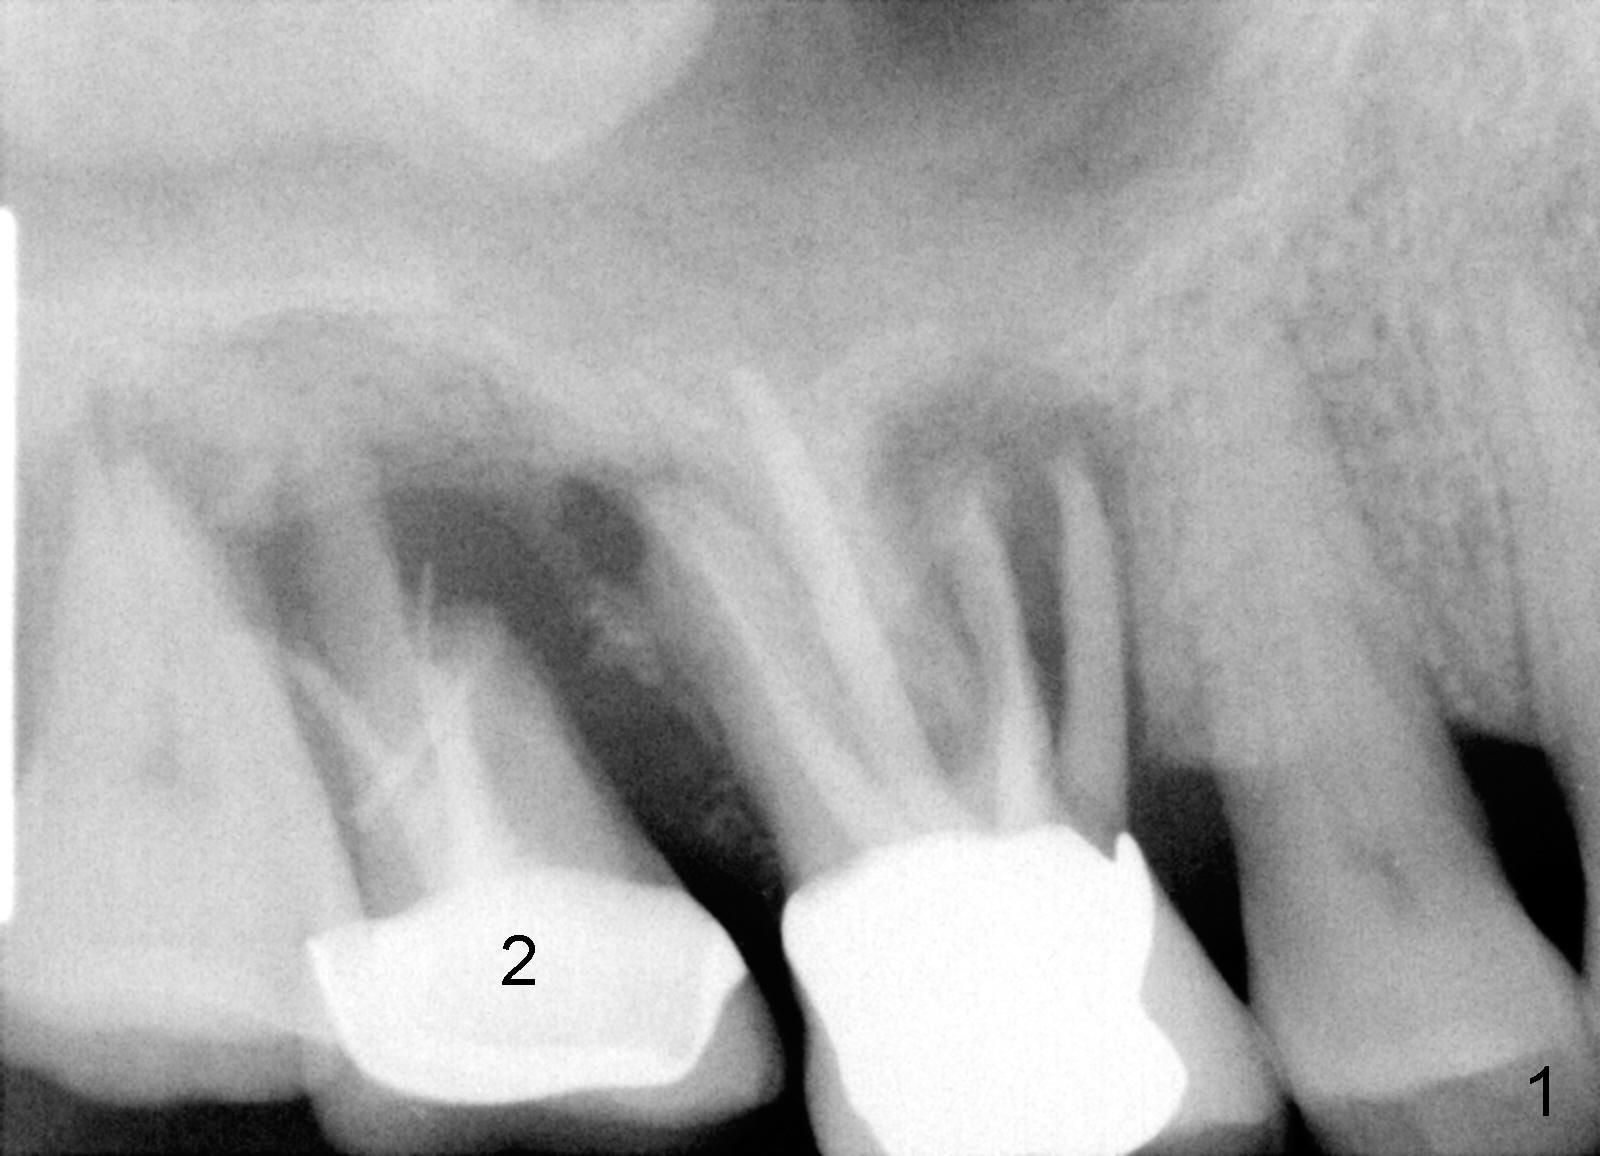

Six months post cementation, the patient returns for follow-up (Fig.11-14) with chief complaint of food impaction between the upper right last 2 teeth. It is difficult to remove. The distal 2nd thread appears not to be covered by the bone, whereas the mesial one is (compare Fig.11 arrowheads). The buccal gingiva is apparently within normal limit (Fig.12) except the distal (Fig.13 >). The distolingual gingiva recession is much more severe (Fig.14). There are deep pockets with tenderness in the abnormal sites. The tooth #1 has #2 mobility with tenderness. The patient agrees to have it extracted and restored with an implant, since the tooth #32 is functional. Bone graft will be placed in the lingual aspect of the implant at the site of #2.